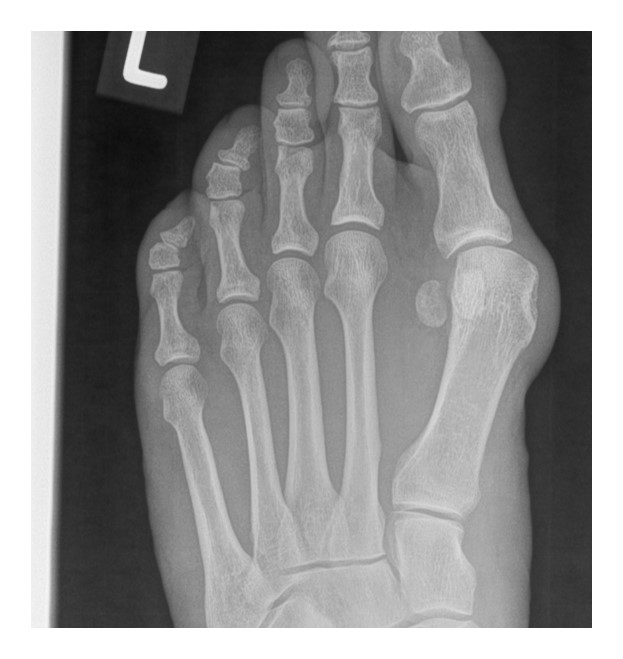

Hallux valgus correction: MAGNEZIX® CS and titanium in a comparison

The x-rays show a hallux valgus on the left foot treated with MAGNEZIX® CS over a period of 1 year post-op. The same procedure was performed on the patient's right foot years earlier with titanium screws which serves as a comparison.